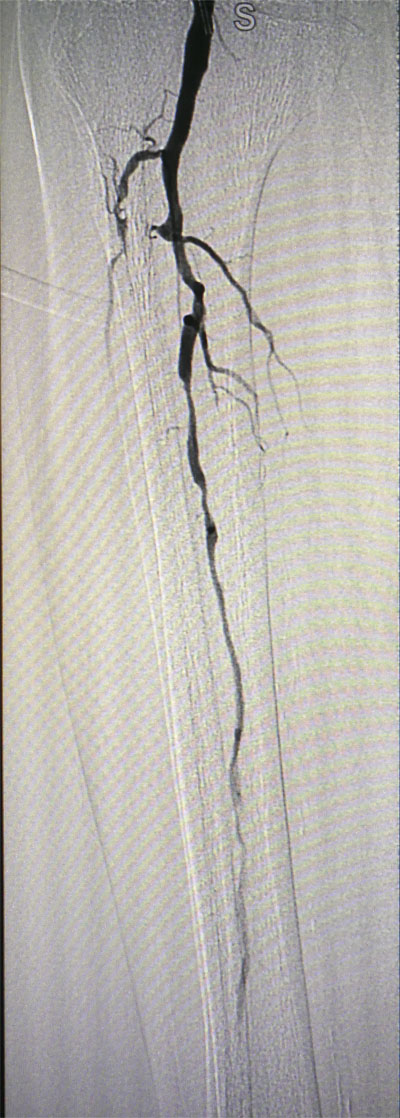

放射科導管室內做好了術前準備,患者由無創呼吸機及各種循環支持下開始介入手術,術中重癥監護科嚴密觀察患者的生命體征,內分泌科醫生負責手術,患者下肢血流極差,膝下僅存一條多處嚴重狹窄的腓動脈供血,主要供血的脛前動脈及脛后動脈均長段閉塞,順行穿刺成功后導絲下行困難,故采用踝下脛后動脈逆穿對接技術成功通過病變。經過近5個小時的奮斗,手術順利完成,患者腓動脈及脛后動脈血流通暢,血流直達足底動脈環,患者感到足部逐漸溫暖,術后清創時患者創面血流豐富。

治療前